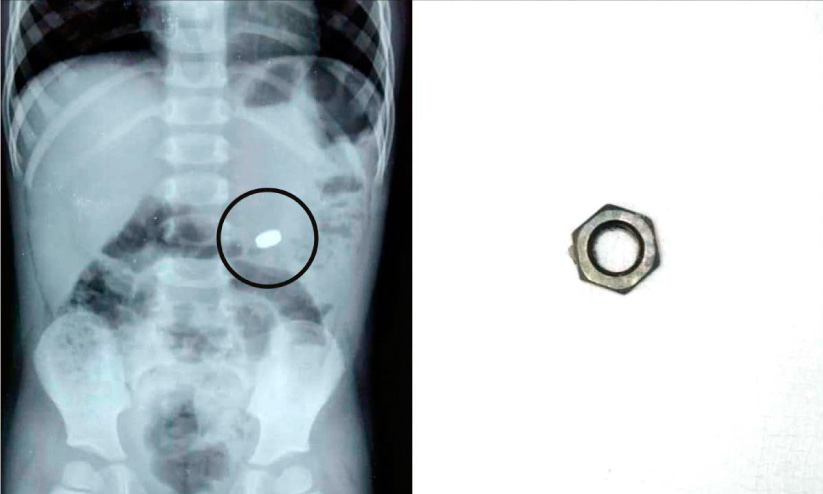

text_fields1. എക്സറേ ചിത്രം 2. വിഴുങ്ങിയ നട്ട്

തൊടുപുഴ: മൂന്ന് വയസ്സുകാരന്റെ ആമാശയത്തിൽ കുടുങ്ങിയ ഇരുമ്പ് നട്ട് പുറത്തെടുത്തു. വെള്ളിയാഴ്ച രാത്രി 12 മണിയോടെയാണ് സംഭവം. കുട്ടി അബദ്ധത്തിൽ നട്ട് വിഴുങ്ങുകയായിരുന്നു. എന്താണ് വിഴുങ്ങിയതെന്ന് വീട്ടുകാർക്ക് ആദ്യം മനസ്സിലായിരുന്നില്ല. ചാഴികാട്ട് ആശുപത്രിയിലെ അത്യാഹിത വിഭാഗത്തില് പ്രവേശിപ്പിച്ച കുട്ടിയുടെ വയറ്റില് നടത്തിയ പ്രാഥമിക പരിശോധനയിലും എക്സ്റേയിലുമാണ് ആമാശയത്തില് കുടുങ്ങിയ നട്ട് കണ്ടെത്തിയത്.

ഗ്യാസ്ട്രോ വിഭാഗത്തിലെ ഡോക്ടര്മാരായ ഡോ. മാത്യു ചൂരക്കന്, ഡോ. ബോണി ജോര്ജ്, എന്ഡോസ്കോപ്പി ടെക്നീഷ്യന് ജോണി എന്നിവരുടെ നേതൃത്വത്തില് രാത്രി രണ്ടുമണിയോടെയാണ് പീഡിയാട്രിക് എന്ഡോസ്കോപ്പി വഴി 1.5 സെന്റീ മീറ്റര് വലിപ്പമുള്ള നട്ട് പുറത്തെടുത്തു. ഒരു ദിവസത്തെ നിരീക്ഷണത്തിനുശേഷം കുട്ടി ആശുപത്രിവിട്ടു.